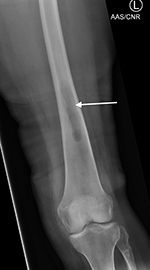

Right tibia bone graft

43 year-old man with comminuted right tibia and fibula fractures as well as extensive bone loss and soft tissue injury. A tibial intramedullary nail with proximal and distal locking screws is present as well as multiple rounded bony allografts. There are also large skin staples.